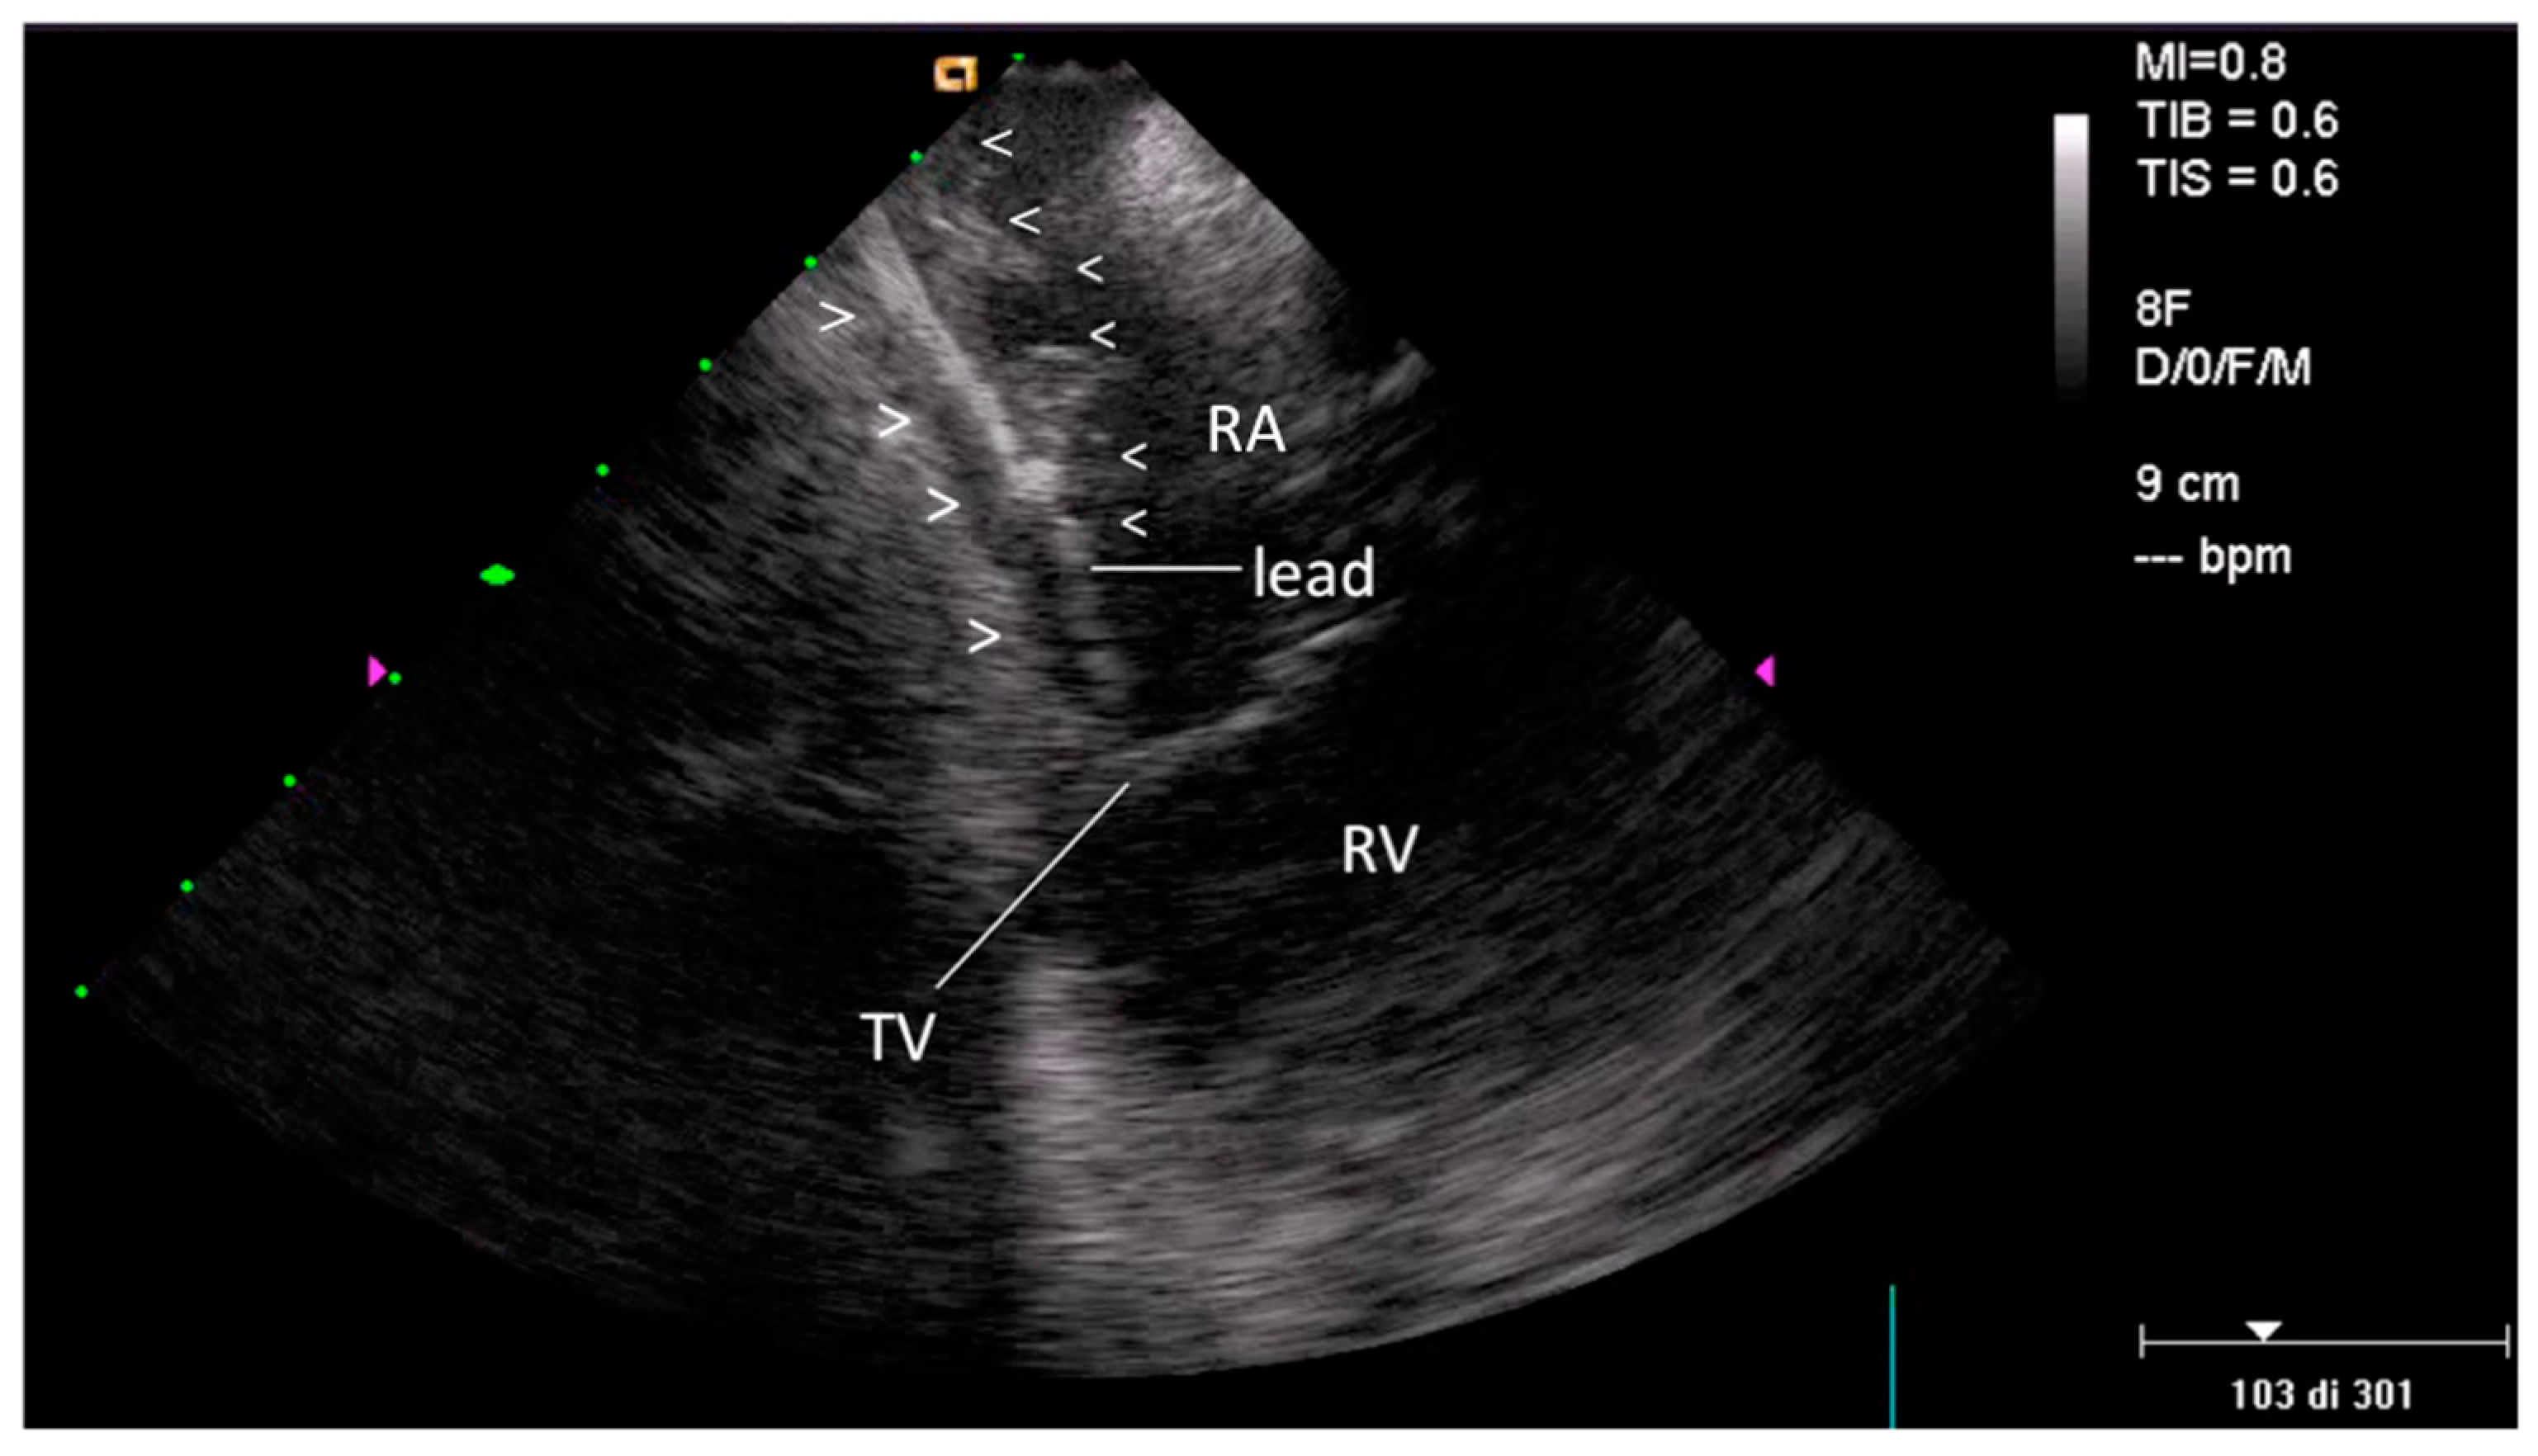

2.2.1. Before Extraction

3.1. Pre-extraction

3.2. Post-extraction ICE